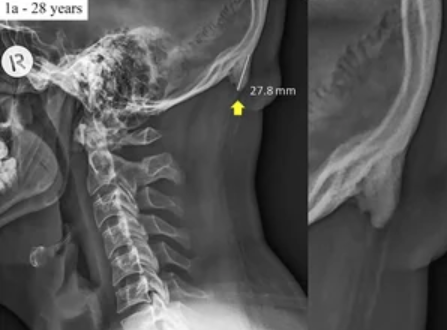

A new study carried by some scientists suggests that wrong body posture that happens because of the usage of the phone is causing a bone called enlarged external occipital protuberance” (EEOP) to develop out on the base of our skull.

While the experts wanted to know how prevalent the bones are, the Australian scientists took out a research and found out that 33% of people falling in the age group of 18 to 86 have a development in their enlarged external occipital protuberance” (EEOP).